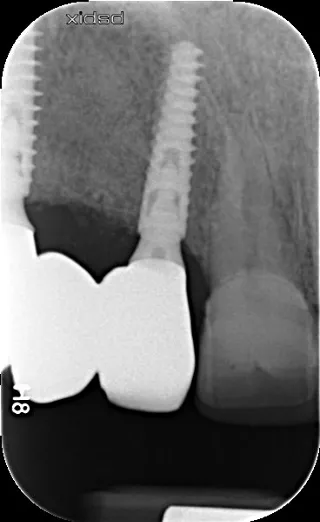

17a-b-c-d. Retro-alveolar X-rays at the end of treatment. Note bone behavior around the 4 implant collars. Soft tissue height above each collar was 3 to 4 mm.

5a-b. Implants were placed away from the edge of the vestibular bone, 0.5 to 1.5 mm subcrestally, so that the implant collar lay 3 mm apical to the collar of the removable overdenture teeth. The design of the Axiom X3® implant limits insertion-related stresses in the bone and thus favors bone preservation. In this clinical situation of average bone density, the Axiom X3® drilling protocol is shortened without the need to use the final drill. Final insertion of each implant was carried out by hand using the ratchet wrench and primary stability was correct.

4a-b. Healing 5 months later. The patient wore a removable overdenture. Vestibular ridge resorption was moderate and bone volume, estimated using CBCT, was sufficient to allow the placement of Axiom X3® Ø 3.4 mm implants in positions 12 and 22 and Ø 4 mm implants in positions 14 and 24.